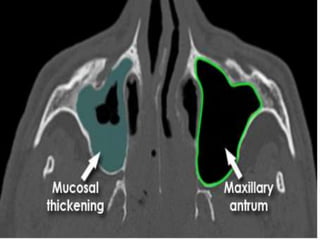

• Paranasal sinuses and mastiod are structures that

are hypodense in normal cases.

Disorders of Sinuses

• Acute bacterial sinusistis.

• Chronic purulent sinusitis.

• Fungal infection.

• Mucocoele.

• Tumors.

Maxillary sinus

Maxillary sinus disease